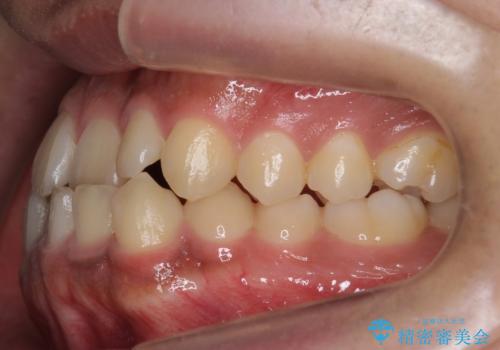

骨格性の受け口 非抜歯で下の歯を後ろに下げる インビザラインで インプラント矯正

- 受け口を主訴に来院。

他院でマウスピース矯正を始めたが、担当医に不信感をもち転院。

治療により受け口が改善し、下あごの輪郭も若干後ろに下がった印象になりました。

当院では下の歯を後ろに下げるため矯正用ミニスクリューを用いてしっかり移動を行う等ご説明をし、治療開始しました。